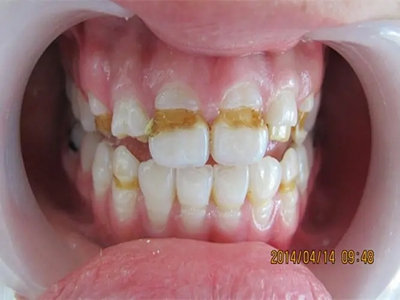

牙釉质发育不全牙齿上深褐色的纹图

牙釉质发育不全初期可出现牙齿色泽和透明度的改变,牙齿透光度下降,表面出现棕褐色的条状凹陷,一般无敏感、疼痛等自觉症状。

牙釉质发育不全牙齿表面有白斑和小坑图

牙釉质发育不全患者牙齿表面出现多处白斑,形成白垩色釉质,同时牙面有不规则的黄色小坑,一般无自觉症状,患者应注意口腔卫生,预防龋病。